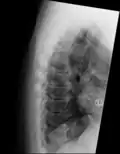

| DISH in an 80 year old female, also with T11 fracture. | |